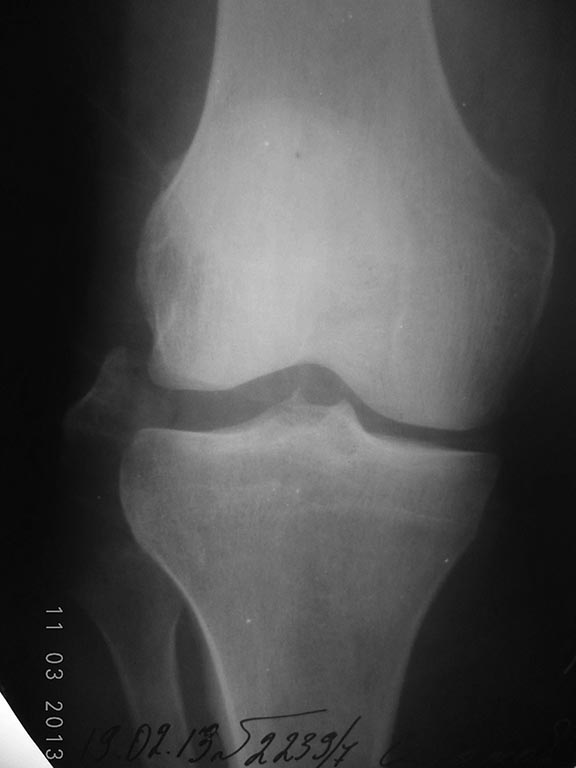

Мужчина 1961 г. р., травма дорожная. Перелом головки малоберцовой кости

со смещением отломков. Помогите определится в тактике оперативного

лечения и его объёме. Заранее спасибо.